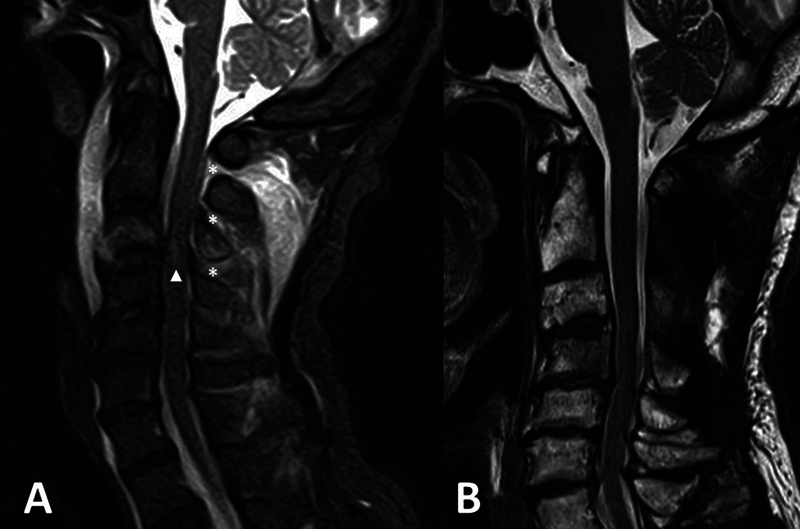

后Ponticulus posticus (PP),也被称为弓形孔,是寰枢椎(C1)的一种解剖变异,是寰枢-枕后膜的骨化,椎动脉(VA) V3段穿过寰枢椎后膜。PP患者在C1侧块内放置多轴螺钉被认为是有风险的,因为可能存在VA损伤的风险。我们报告一例双侧PP,后路固定治疗不稳定的上颈椎损伤。患者,70岁男性,持续跌倒引起的不稳定上颈椎损伤(外伤性C2椎体滑脱伴C3-4小关节单侧脱位)。在最初的保守治疗后,在亚急性期进行了后路固定手术。术前图像显示双侧PP存在。因此,放弃了将螺钉置入C1侧块的原计划,改为将椎板钩置入一侧,将螺钉置入另一侧的C1后弓。他的术后过程很顺利,受伤后27天他被转移到康复医院。在伴有PP的上颈椎不稳病例中,必须根据损伤程度和VA病程逐一考虑固定方法。

Ponticulus posticus (PP), also known as arcuate foramen, is an anatomical variation of the atlas (C1), which is an ossification of the posterior atlanto-occipital membrane and through which the V3 segment of the vertebral artery (VA) runs. Placement of a polyaxial screw in the C1 lateral mass is considered risky in those with PP because of possible risk for VA injury. We report a case with bilateral PP in which posterior fixation for unstable upper cervical spine injury was performed. The patient, a 70-year-old man, sustained a fall-induced unstable upper cervical spine injury (traumatic C2 spondylolisthesis with unilateral dislocation of the C3-4 facet joint). Following initial conservative treatment, a posterior fixation surgery was performed in the subacute phase. Preoperative images revealed the presence of bilateral PP. Therefore, an original plan to place the screws in the C1 lateral mass was discarded, and instead, placement of the laminar hook on one side and placement of the screw into the C1 posterior arch on the other side was performed. His postoperative course was uneventful, and he was transferred to a rehabilitation hospital 27 days after the injury. In cases of upper cervical spine instability with concomitant PP, it is essential to consider the fixation method based on the extent of the injury and the course of the VA on a case-by-case basis.